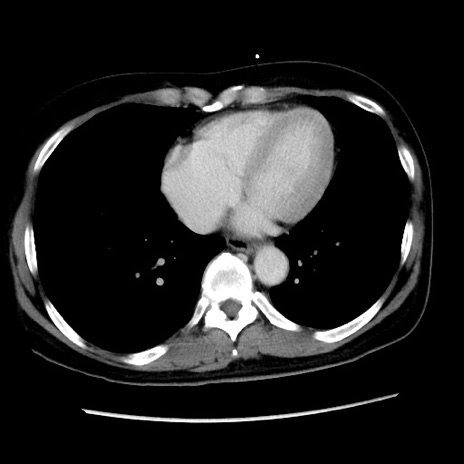

冠状断像

症例10(横断像)

【症例】 50歳代女性

【主訴】 腹痛

【現病歴】前日生レバーを食べた。今朝に排便あり。 昼前に突然発症の腹痛を生じ、当院救急外来を受診した。

【身体所見】 意識清明、腹部:平坦、軟、下腹部やや左を中心に圧痛・反跳痛あり、筋性防御あり

【データ】WBC 7800、CRP 0.07